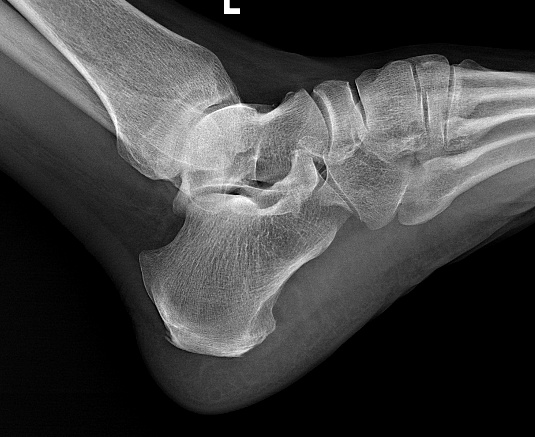

足底筋膜位于脚底,连接足跟和脚趾,平时负责支撑足弓、缓冲压力。长期受力过多、反复牵拉后,筋膜在足跟附着处就容易劳损,时间久了,就会出现疼痛。最典型的表现,就是晨起第一步痛、久坐后起身痛、走远了更痛。

对于这类顽固性足跟痛患者,神经射频消融术提供了一个微创选择。它不是传统意义上的“大手术”,也不是把脚底切开,而是在精准定位下,用很细的射频针作用于疼痛相关神经靶点,减轻疼痛信号传导,从而达到镇痛效果。